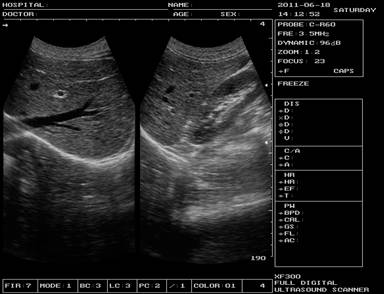

Affordable Easy Operate Full Digital Portable Ultrasound Scanner

Images

Full Digital Portable Ultrasound Equipment / Mobile Ultrasound Machine Images |